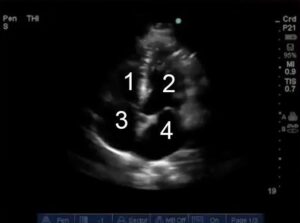

Parasternale asse corto (PSAX)

Piano di scansione perpendicolare all’asse lungo del ventricolo sinistro, che mostra una sezione trasversale di entrambi i ventricoli. È possibile ottenere questa scansione a diverse altezze, quella più usata nella tecnica POCUS è a livello dei muscoli papillari (circa a metà altezza del ventricolo), ma spostandosi cranialmente è possibile visualizzare anche le tre cuspidi della valvola aortica.

Posizione della sonda

Mantenendo la sonda sulla finestra parasternale per la visione dell’asse lungo, questa visione è ottenuta ruotando la sonda di circa 90° fino a puntare l’indicatore verso la spalla sinistra del paziente.

Prendendo in considerazione la porzione anteriore, laterale, inferiore e settale del cuore, in questa proiezione sono apprezzabili segmenti di tutti i territori di irrorazione delle arterie coronarie destra e sinistra (che si divide in discendente anteriore e circonflessa)

- Ventricolo destro

- Ventricolo sinistro

- Muscoli papillari

L’asse corto parasternale fornisce informazioni importanti sulla funzionalità globale e regionale del ventricolo e sul suo riempimento:

- In condizioni normali i vari segmenti delle pareti del ventricolo sinistro si ispessiscono tutte allo stesso modo durante la sistole. Ispessimento ridotto o assente possono indicare ischemia o infarto coronarico. Tipicamente la coronaria discendente anteriore irrora la porzione anteriore, la circonflessa la porzione laterale e la coronaria destra la porzione posteriore del cuore. In condizioni di ridotto ritorno venoso il ventricolo sinistro si presenta piccolo, scarsamente riempito e ipercinetico, mentre un ventricolo pieno in diastole e che si svuota completamente in sistole può suggerire uno stato di alta portata cardiaca. Questa visione è solitamente utilizzata per fare una stima spannometrica di quanto possa essere la frazione di eiezione del ventricolo sinistro.

- Il ventricolo destro non è valutato idealmente da questa finestra, ma se si presenta di dimensioni notevolmente maggiori rispetto al sinistro può suggerire anomalie del circolo polmonare. Sovraccarichi di pressione o di volume del ventricolo destro possono determinare alterazioni del movimento del setto interventricolare.

- Il setto interventricolare normalmente appare convesso verso il ventricolo destro, in quanto le pressioni nel ventricolo sinistro sono maggiori di quelle nel ventricolo destro in condizioni fisiologiche. Se il setto appare piatto in diastole può indicare uno stato di sovraccarico di volume del ventricolo destro), mentre se il setto appare piatto sia in diastole che in sistole, può indicare una condizione di severa ipertensione polmonare.

- Anche in questa visione è possibile talvolta apprezzare versamento pericardico come una zona anecogena anteriormente al miocardio.